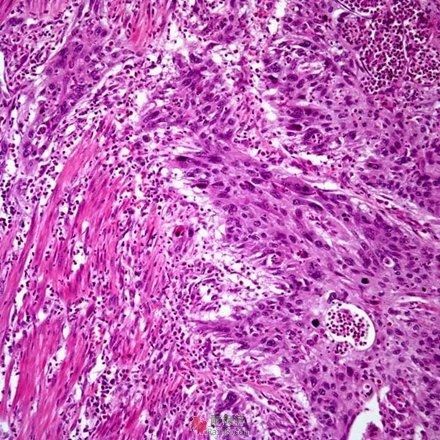

根据肿瘤细胞和组织显微镜下这些和其他一些的病理组织学特征,医生为大多数癌症设定和分配一个“级别”数值。 因此,癌症的分级也称病理学分级,就是癌症细胞和组织的“不正常程度”,或者“与正常细胞组织差异性程度”,是反应肿瘤生长和扩散速度的一个指标,简单来说所代表的是肿瘤的“侵犯性或进展性潜力”,通俗来说就是其恶性程度的大小。 癌症的分级与分期相对于癌症的分级,普通公众对于癌症的分歧可能更熟悉一些,就是人们常说的某某人的癌症是早期还是晚期。 癌症分期就是肿瘤所处的发展阶段,主要指原发肿瘤的大小、累及范围和是否已经扩撒。通常根据原发肿瘤的位置、大小、区域淋巴结是否受到侵犯累及,以及肿瘤的数目(也就是是否产生转移)这几个因素来确定。 如何获得肿瘤的分级?如果怀疑一个肿瘤是恶性的,医生会采取一个被称为活体组织病理学检查的方法(简称活检)来确定。这个过程包括医生切除肿瘤的部分或全部组织,由病理学医生把获得组织切成非常薄的切片,通常还进行染色等其他处理后在显微镜下对于细胞形态和组织结构进行观察,以确定肿瘤是恶性还是良性,同时还根据组织病理学特征进行病理学分级,即确定恶性程度等级。 如何划分肿瘤级别?由于癌症的组织病理学可能存在巨大差异,因此不同癌症可能会使用不同的分级系统。但是,在一般情况下,根据组织学上的异常程度,肿瘤被分为G1、G2、G3、G4等几个级别。 G1肿瘤为低级别肿瘤,细胞和组织形态接近于正常,这些肿瘤往往生长和扩散缓慢。与此相反,G3和G4肿瘤的组织学形态看起来与正常细胞和组织差异更大,称为高级别肿瘤,通常比低级别肿瘤生长和扩散更迅速。G2肿瘤则为中级别肿瘤。 非特定类型肿瘤通常的通用分级系统为: GX:级别无法评定(未定级); G1:高分化(低级别); G2:中度分化(中级别); G3:低分化(高级别); G4:未分化(高级别)。 ![]() 低级别(I级)乳腺 ![]() 高级别(III级)乳腺癌 高级别(III级)乳腺癌可见,肿瘤分级中的级别高低与分化程度的高低恰恰相反,分化程度越高级别越低,恶性程度也就越低;相反,分化程度越低级别越高,恶性程度也就越高。具体到徐才厚的“膀胱高级别尿路上皮癌”就是低分化程度、恶性程度高的膀胱癌。 ![]() 低级别膀胱移行细胞癌 ![]() 浸润性膀胱高级别尿路上皮癌 癌症分级的意义癌症的分级就是微观组织病理学上的异常性程度,也就是其恶性程度,通常反应肿瘤的生长和扩散速度。 掌握正确的癌症分级信息可以帮助医生结合诸如癌症所处的阶段(即分期),患者的年龄、一般健康状况来制定治疗方案计划,并确定患者的预后(即疾病可能的结果或过程,以及恢复或复发的机会)。通常,较低级别预示预后较好;更高级别的癌症预示生长和扩散更迅速,预后更差,相应的可能需要更及时或更积极的治疗。 癌症的分期什么是癌症的分期? 癌症是从单一的癌细胞发展来的。从癌细胞的出现,通过不断分裂增生形成肿瘤,发展到临床上可以检查出的肿块以及出现临床症状,乃至侵犯和转移其他组织部位,通常需要一个长达十数年到数十年的长期过程,因此癌症被归于一种慢性疾病。 |